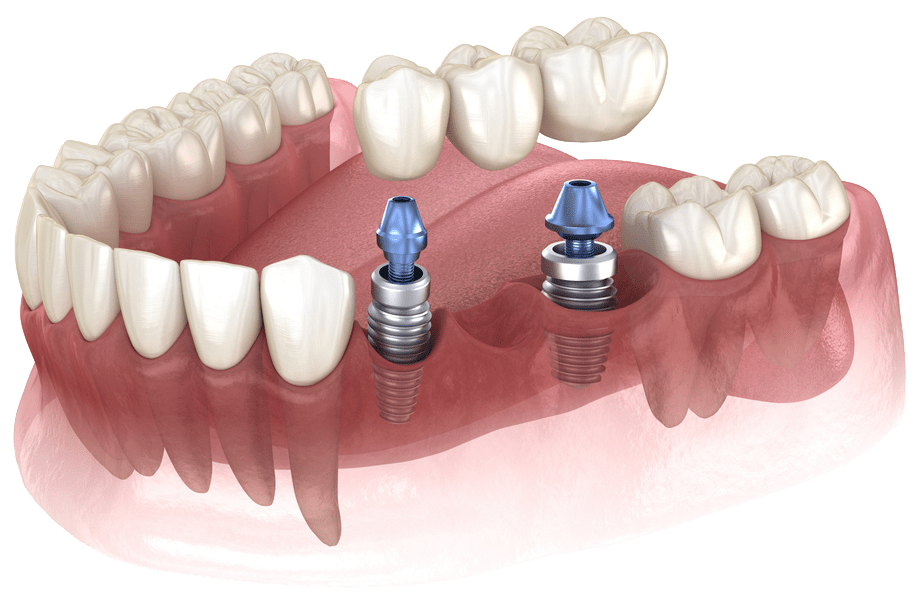

Dental Implants: Restoring

Function and Aesthetics

Dental implants are amongst the best solutions for replacing missing teeth. At Shore Side Family Dentistry, we use state-of-the-art techniques to place titanium implants that integrate with the jawbone, thereby providing a stable foundation for prosthetic teeth that not only function but look like natural teeth.

The Dental Implant Process

Initial Consultation

A thorough examination and consultation to determine the best treatment plan.

Implant Placement

In this stage, titanium posts are surgically placed into the jawbone.

Healing Period

In the next stage, the implants fuse with the bone in a process called osseointegration.

Abutment Placement

A connector post is attached to the implant.

Restoration

The final crown, bridge, or denture is placed, completing the restoration.